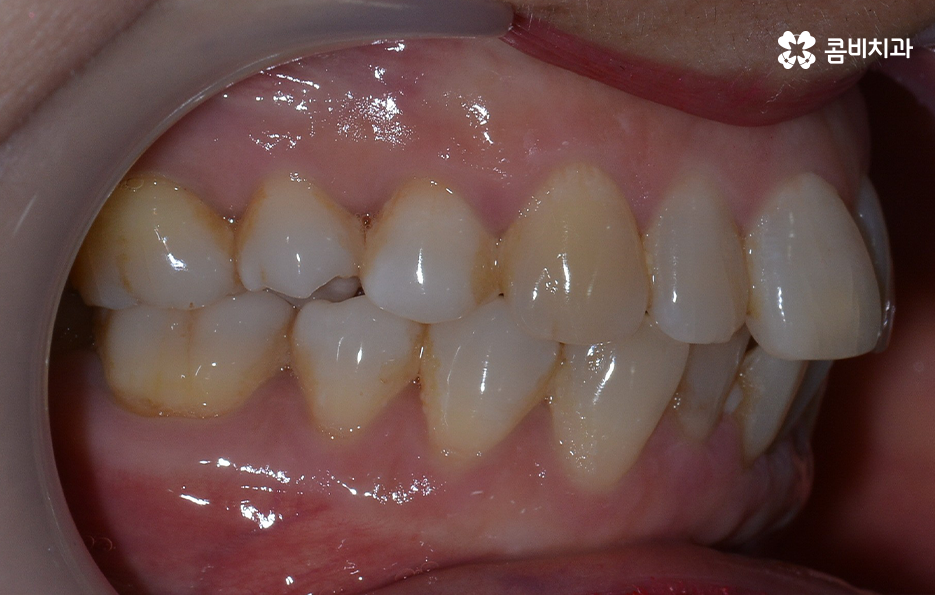

오늘 보시는 교정 사례의 경우를 보시면 아랫니의 틀어짐도 크지만 측면 사진으로 보시면 치열로 인해 돌출입에 영향을 준다는 사실도 알 수 있어요. 즉 치열과 함께 돌출입도 함께 고치고 싶어하기 때문에 치열도 재배열 하지만 치아 안쪽으로 넣어서 입술라인과 얼굴형으로 볼 때도 돌출입도 치료하는 치료 계획을 세웠기 때문에 작은 어금니 발치를 통한 치아의 이동 공간을 확보한 사례로 볼 수 있어요

치아교정의 원리를 생각하면 치아를 안쪽으로 넣어야 하는 치료 계획을 세울 때 치아가 이동할 수 있는 공간을 확보해야 하고 특히 얼굴형까지 고려하여 치아를 크게 이동시켜야 할 때는 발치 교정이 꼭 필요할 수 있는데요